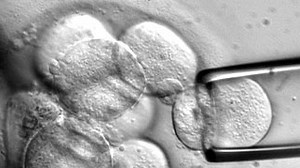

A Stem Cell Story

What are stem cells, where do they come from, and what do we really know about them? An award-winning introduction to the world of stem cell research. Innovative hand-drawn animation, beautiful cell photography and documentary interviews capture the fascination and complexity of this cutting-edge area of science. Best TV/video production ...

Stem Cells- Definition, Properties, Types, Uses, Challenges

microbenotes.com

Stem Cell Sources, Types, and Uses in Research

news-medical.net